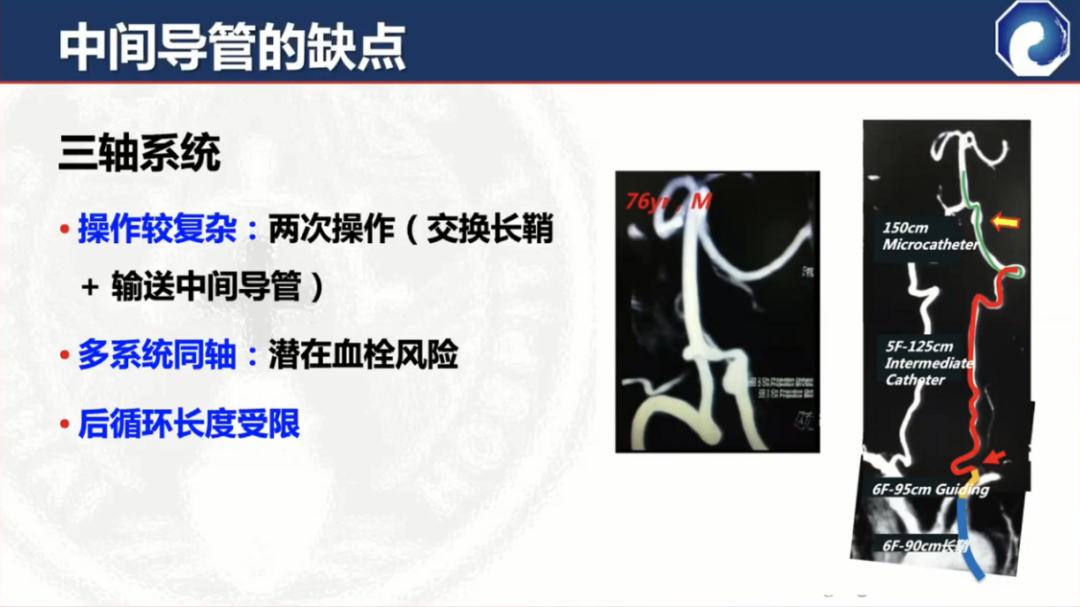

此外,中间导管的支撑力比较差,近端需加长鞘或8F Guiding做支撑,需三轴系统

三轴系统的缺点: